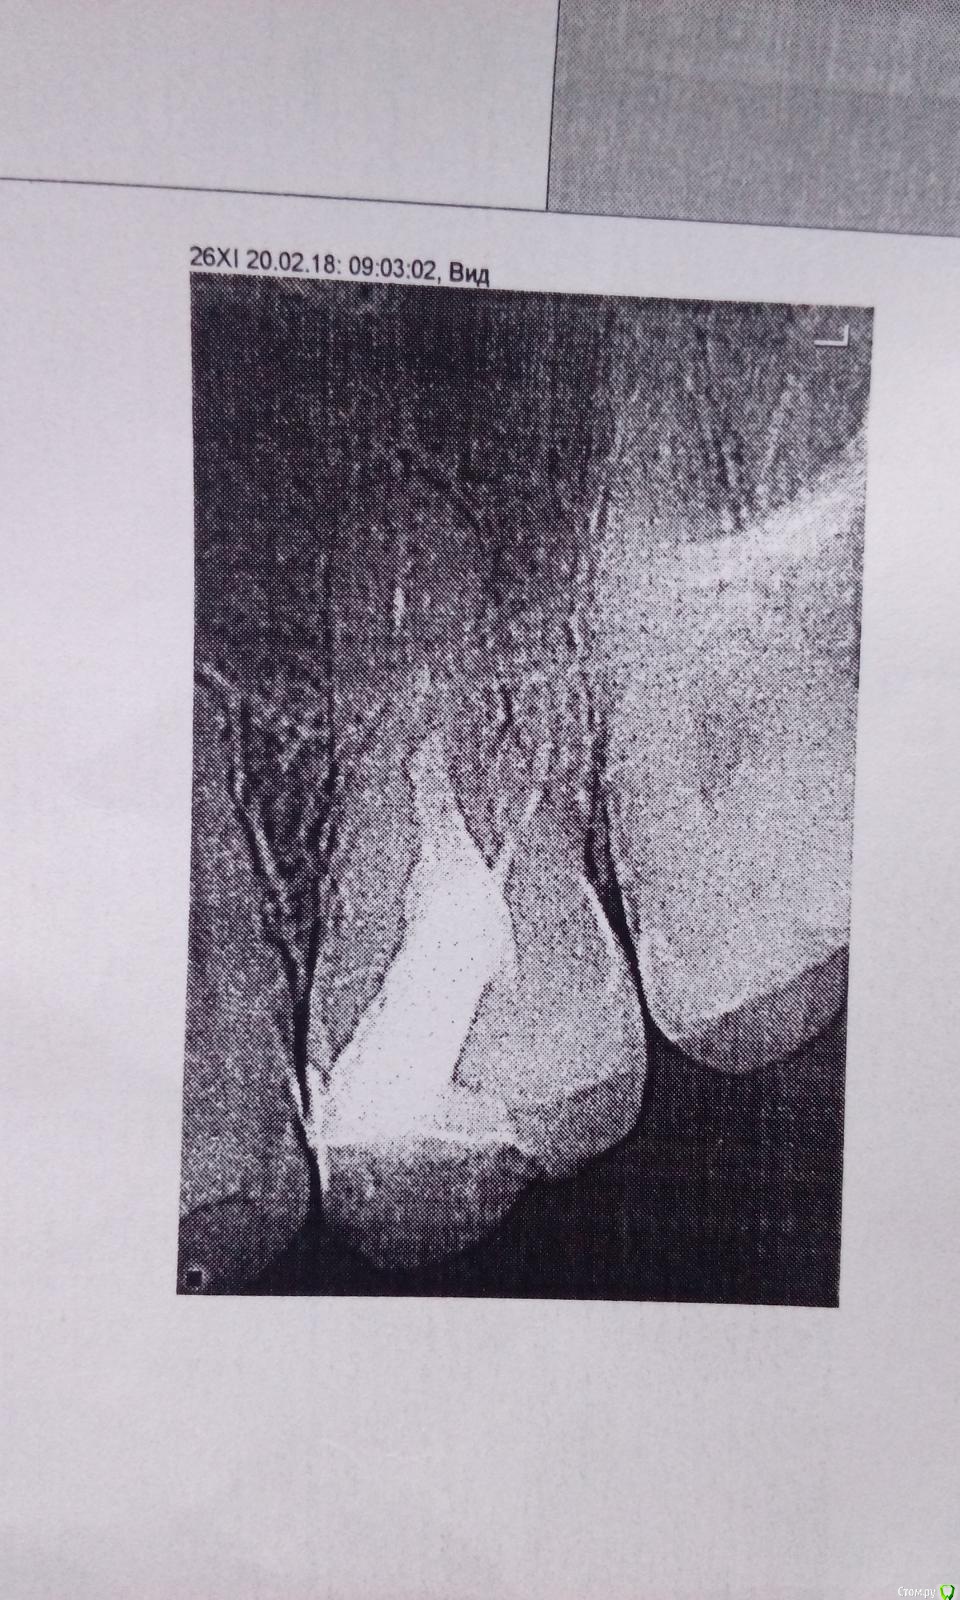

Катя М. Опубликовано 20 февраля, 2018 Поделиться Опубликовано 20 февраля, 2018 Здравствуйте,лечу верхнюю шестерку слева.депульпировали,запломбировали.Щеками опухла и болела,стоматология назначил антибиотик-5дней.Боль прошла.Через неделю опять стал болеть-ноет и распирает.Сделала снимок зуба,говорят все в порядке.Другой стоматолог сказал что один канал не запломбирован.Зуб болит,немного реагирует на холодное,уже и лицо стало ныть на этой стороне.Посмотрите пожалуста,не знаю что делать и к кому идти Ссылка на комментарий

red_butler Опубликовано 20 февраля, 2018 Поделиться Опубликовано 20 февраля, 2018 Требуется повторное лечение 2 Ссылка на комментарий